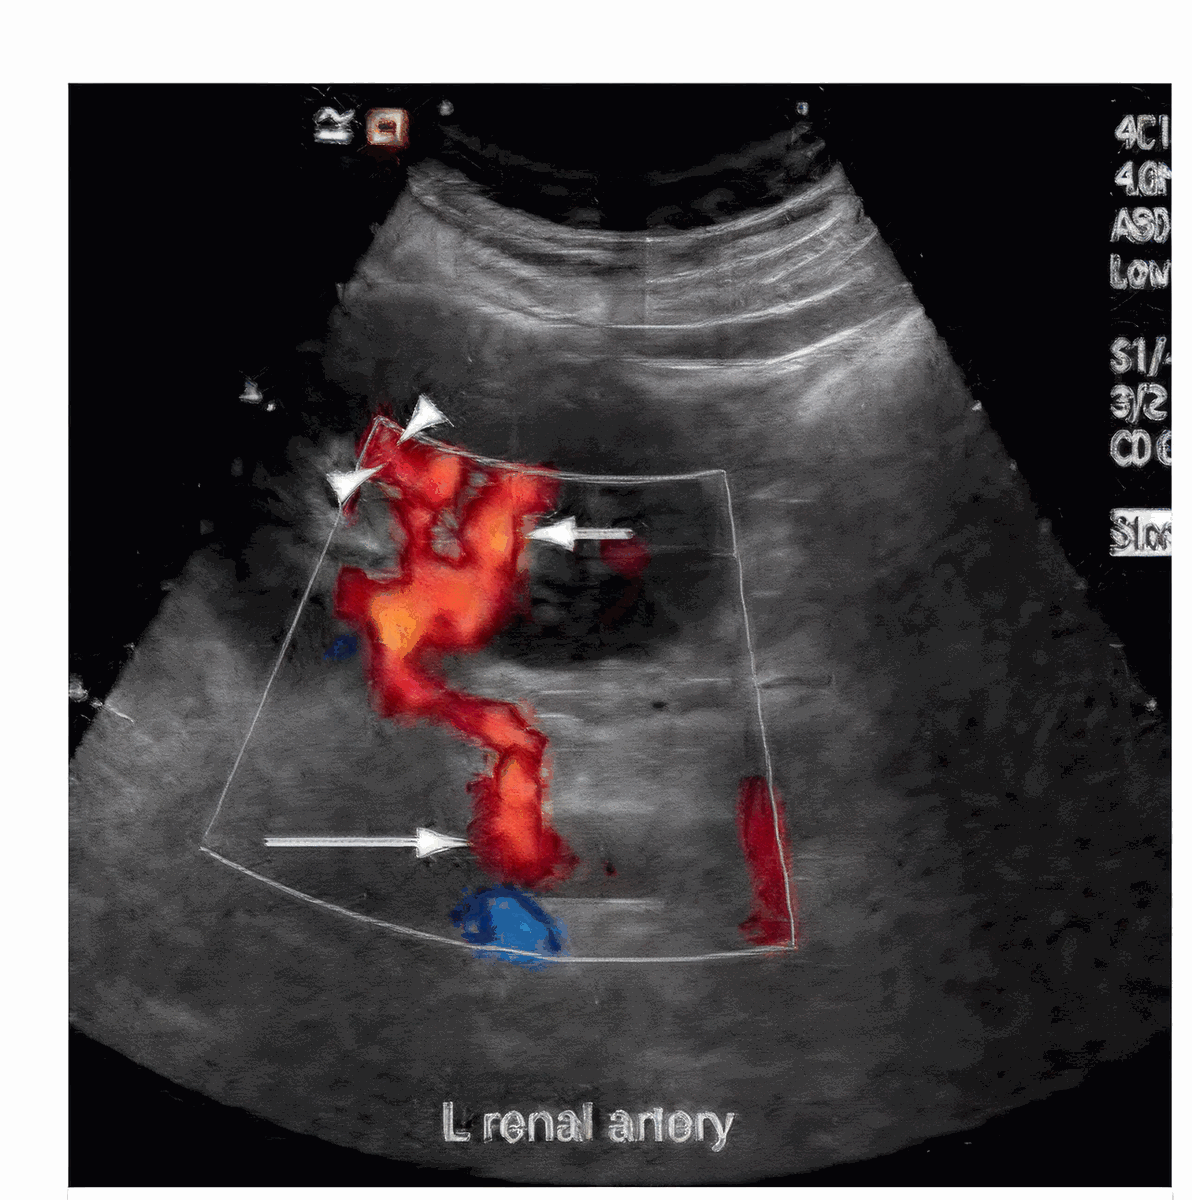

Дослідження ниркових артерій

Доплерографія ниркових артерій в діагностиці симптоматичної гіпертензії та розладів кровоплину нирок.

800 грн